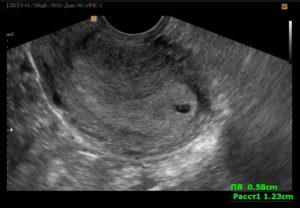

Как уже упоминалось, этот диагноз звучит всегда при УЗИ обследовании. Никаким другим способом его не поставить. Врач УЗИ видит плодное яйцо с полостью, но не видит эмбрион и сердцебиение.

Как известно, при УЗИ на раннем сроке в полости плодного яйца должно быть два образования, желточный мешок и рядом с ним эмбрион. Желточный мешочек при анэмбрионии может определяться, но сам эмбрион не виден. Если УЗИ сделали очень рано, возможна ошибка, поэтому его стоит повторить через неделю или две.

Во втором случае специалисты говорят о том, что нарушение развития эмбриона происходит на ранних сроках, не позднее 4-5 недель гестации. Если у пациентки в полости матки при УЗИ визуализировано плодное яйцо без эмбриона, следует предположить либо малый срок развивающейся беременности, либо анэмбрионию.

После оплодотворения плодное яйцо имплантируется в стенку матки, однако эмбрион не растет или же развивается с сильной задержкой. Во время ультразвукового исследования отмечается увеличивающаяся в размерах матка, утолщающийся эндометрий и пустое плодное яйцо. Обычно его диаметр составляет около 20-25 мм.